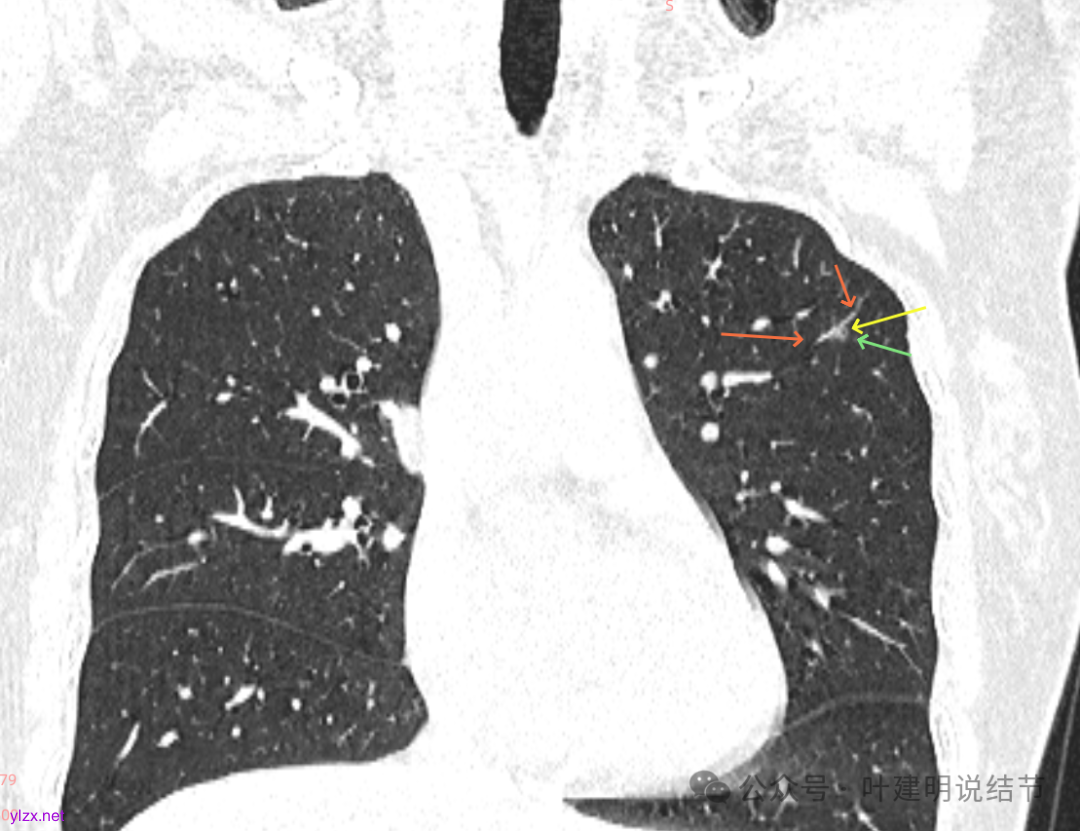

再看2020年5月时的主病灶以及两次对比的影像:

上图示对比,密度略有增加,但并不十分厉害。

两肺多发磨玻璃结节,我们主要看最主要的病灶有没有风险或者有没有进展就可以。我是先看2025年的,黄色的微小磨玻璃结节,密度很低,但是轮廓较为清楚,需要考虑肺泡上皮增生或者肺泡间隔增宽,严格意义上应该没有算肺癌,但是以后有可能会发展到不典型增生或者原位癌,当然也可能永远发展不到那个程度,所以目前不需要管;蓝色的到底是肺泡上皮增生还是少许慢性炎不太好确定,因为轮廓稍显模糊,但它又是磨玻璃密度,总归近期是能够随访的;橘色的密度比黄色的略高,有可能会使肺泡上皮增生或者不典型增生,目前也仍可以随访;粉色的是主病灶,位于左肺上叶,混合密度,表面毛糙,由小血管进入,单次看需要考虑微浸润性腺癌可能性较大。然后我们再来看2020年的影像,因为除了粉色的其他的都没有风险,所以不需要一一去找出来,重点关注粉色这处当时是怎样的。我们发现这个病灶5年前就有,也有小血管进入,也有表面毛糙,也是磨玻璃密度,但是当时磨玻璃当中没有实性的成分,是纯磨玻璃伴微小血管进入。对比起来看,这个病灶在5年当中略有进展,原来应该是腺体前驱病变,现在应该是原位癌或者微浸润性腺癌。那么是不是现在就到了一定得马上手术的程度呢?这个仍然可能是不同医生意见会有出入的。假如说从再随访是不是马上会转移来讲,这么小的肿瘤,发展这么慢,而且仍然含有磨玻璃成分,病理考虑与微浸润性腺癌可能性较大,应该仍然不至于说没有随访的空间。但是如果继续随反思想压力比较大,以及即便在随访后续仍然总得要开刀来说,加上病灶位置靠胸膜并不远,简单的单孔胸腔镜楔形切除就能解决问题,将有一定风险的这个病灶切了,同样是可行的。这需要你自己权衡决定。我没有办法100%给十分确切的意见。但是如果从倾向性来讲,由于是多发病灶,加上年纪还轻,风险还不是很大,稍微清一下雨6~9个月复查,有进展病风险再增加再考虑手术。意见供你参考!